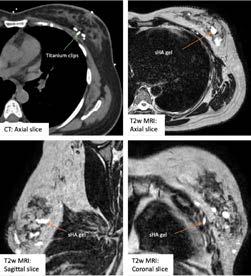

A RANZCR-funded tissue fiducial marker research project is a winner for breast cancer patients.

recently completed project on the efficacy of gel for post-lumpectomy cavity delineation in breast cancer has been a winner for RANZCR early career Fellow Dr Janice Yeh.

Dr Yeh, a radiation oncology consultant at Peter MacCallum Cancer Centre, conducted her project while a Clinical Research Fellow at the Olivia NewtonJohn Cancer and Wellness Centre as part of her PhD. She designed the project to learn if Barrigel, a hyaluronic acid gel used as a tissue fiducial marker, could improve the conformity index among radiation oncologists when contouring the post-lumpectomy tumour bed in breast cancer patients requiring adjuvant breast radiation therapy compared to surgical clips. The findings, that gel insertion as a marker was safe and feasible, and that it's a reliable alternative to surgical clips when MRI simulation planning scan is used, will mean a better outcome for breast cancer patients who undertake breast conserving surgery.

Inside News sat down with Dr Yeh to ask her about the project “As we know, adjuvant radiotherapy after breast conserving surgery plays a key role in the management of breast cancer, the most common cancer affecting women. In early-stage disease, treatment options have expanded to include partial breast irradiation, simultaneous integrated boosts, VMAT/IMRT techniques, and MR-guided radiotherapy. Regardless of technique, accurate tumour bed delineation and dose coverage remains fundamental in achieving optimum oncological outcome. This task has become more challenging as surgical techniques also evolve over time, particularly oncoplastic breast conserving surgery.

“These opportunities have fostered my enthusiasm to remain engaged in future projects.”

“My research investigates the use of hyaluronic acid gel as an alternative novel breast tumour bed marker to surgical clips. The gel is bioresorbable and visible on MRI, making it well suited to MRI-based radiotherapy simulation and treatment. The reliability of surgical clips alone to mark the tumour bed in certain types of oncoplastic breast conserving surgery has been questioned in the literature due to issues of clip migration. It is therefore important that alternative types of fiducial markers be investigated. As hyaluronic acid gel is inserted interstitially into breast tissue, theoretically it would have less risk of migration compared to clips and would warrant further investigation in this setting.